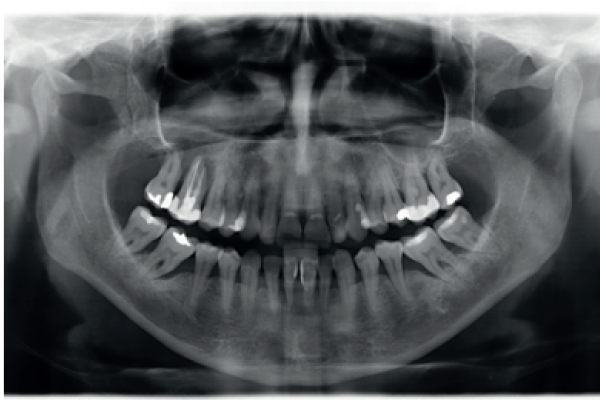

Rehabilitación implantosoportada sobre implantes dentales y cigomáticos en un paciente con radioterapia por un carcinoma adenoide. A propósito de un caso clínico

Extreme vertical and horizontal atrophy combined in posterior mandibular sectors; use of short implants and 2-phase ridge expansion with transitional implants: A clinical case

Atrophic posterior maxilla: sinus elevation with lateral approach Vs. Extra-short implants. Clinical case with eight years of follow-up